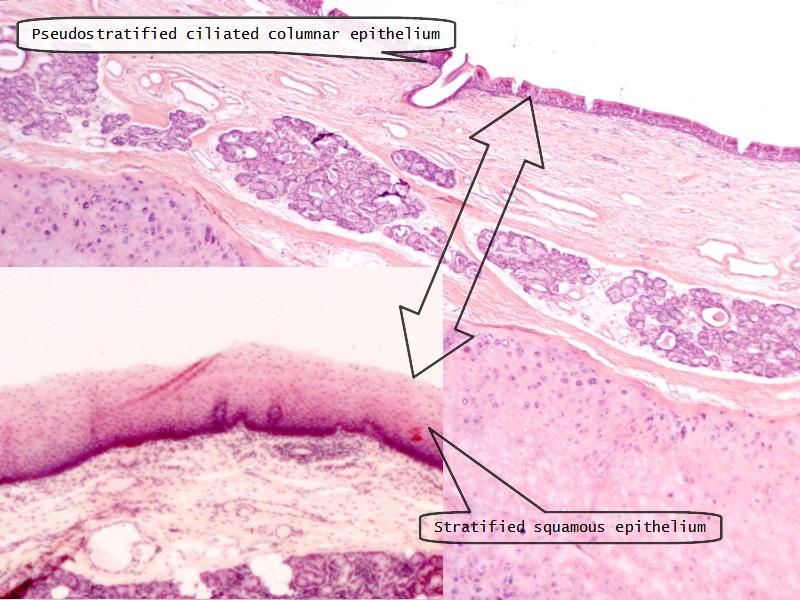

Epiglottis

Respiratory epithelium

- Pseudostratified

- Ciliated

- Columnar

- Epithelium with

- 4 Cells

- Ciliated columnar cells

- Non-ciliated columnar cells

- Goblet cells

- Basal cells